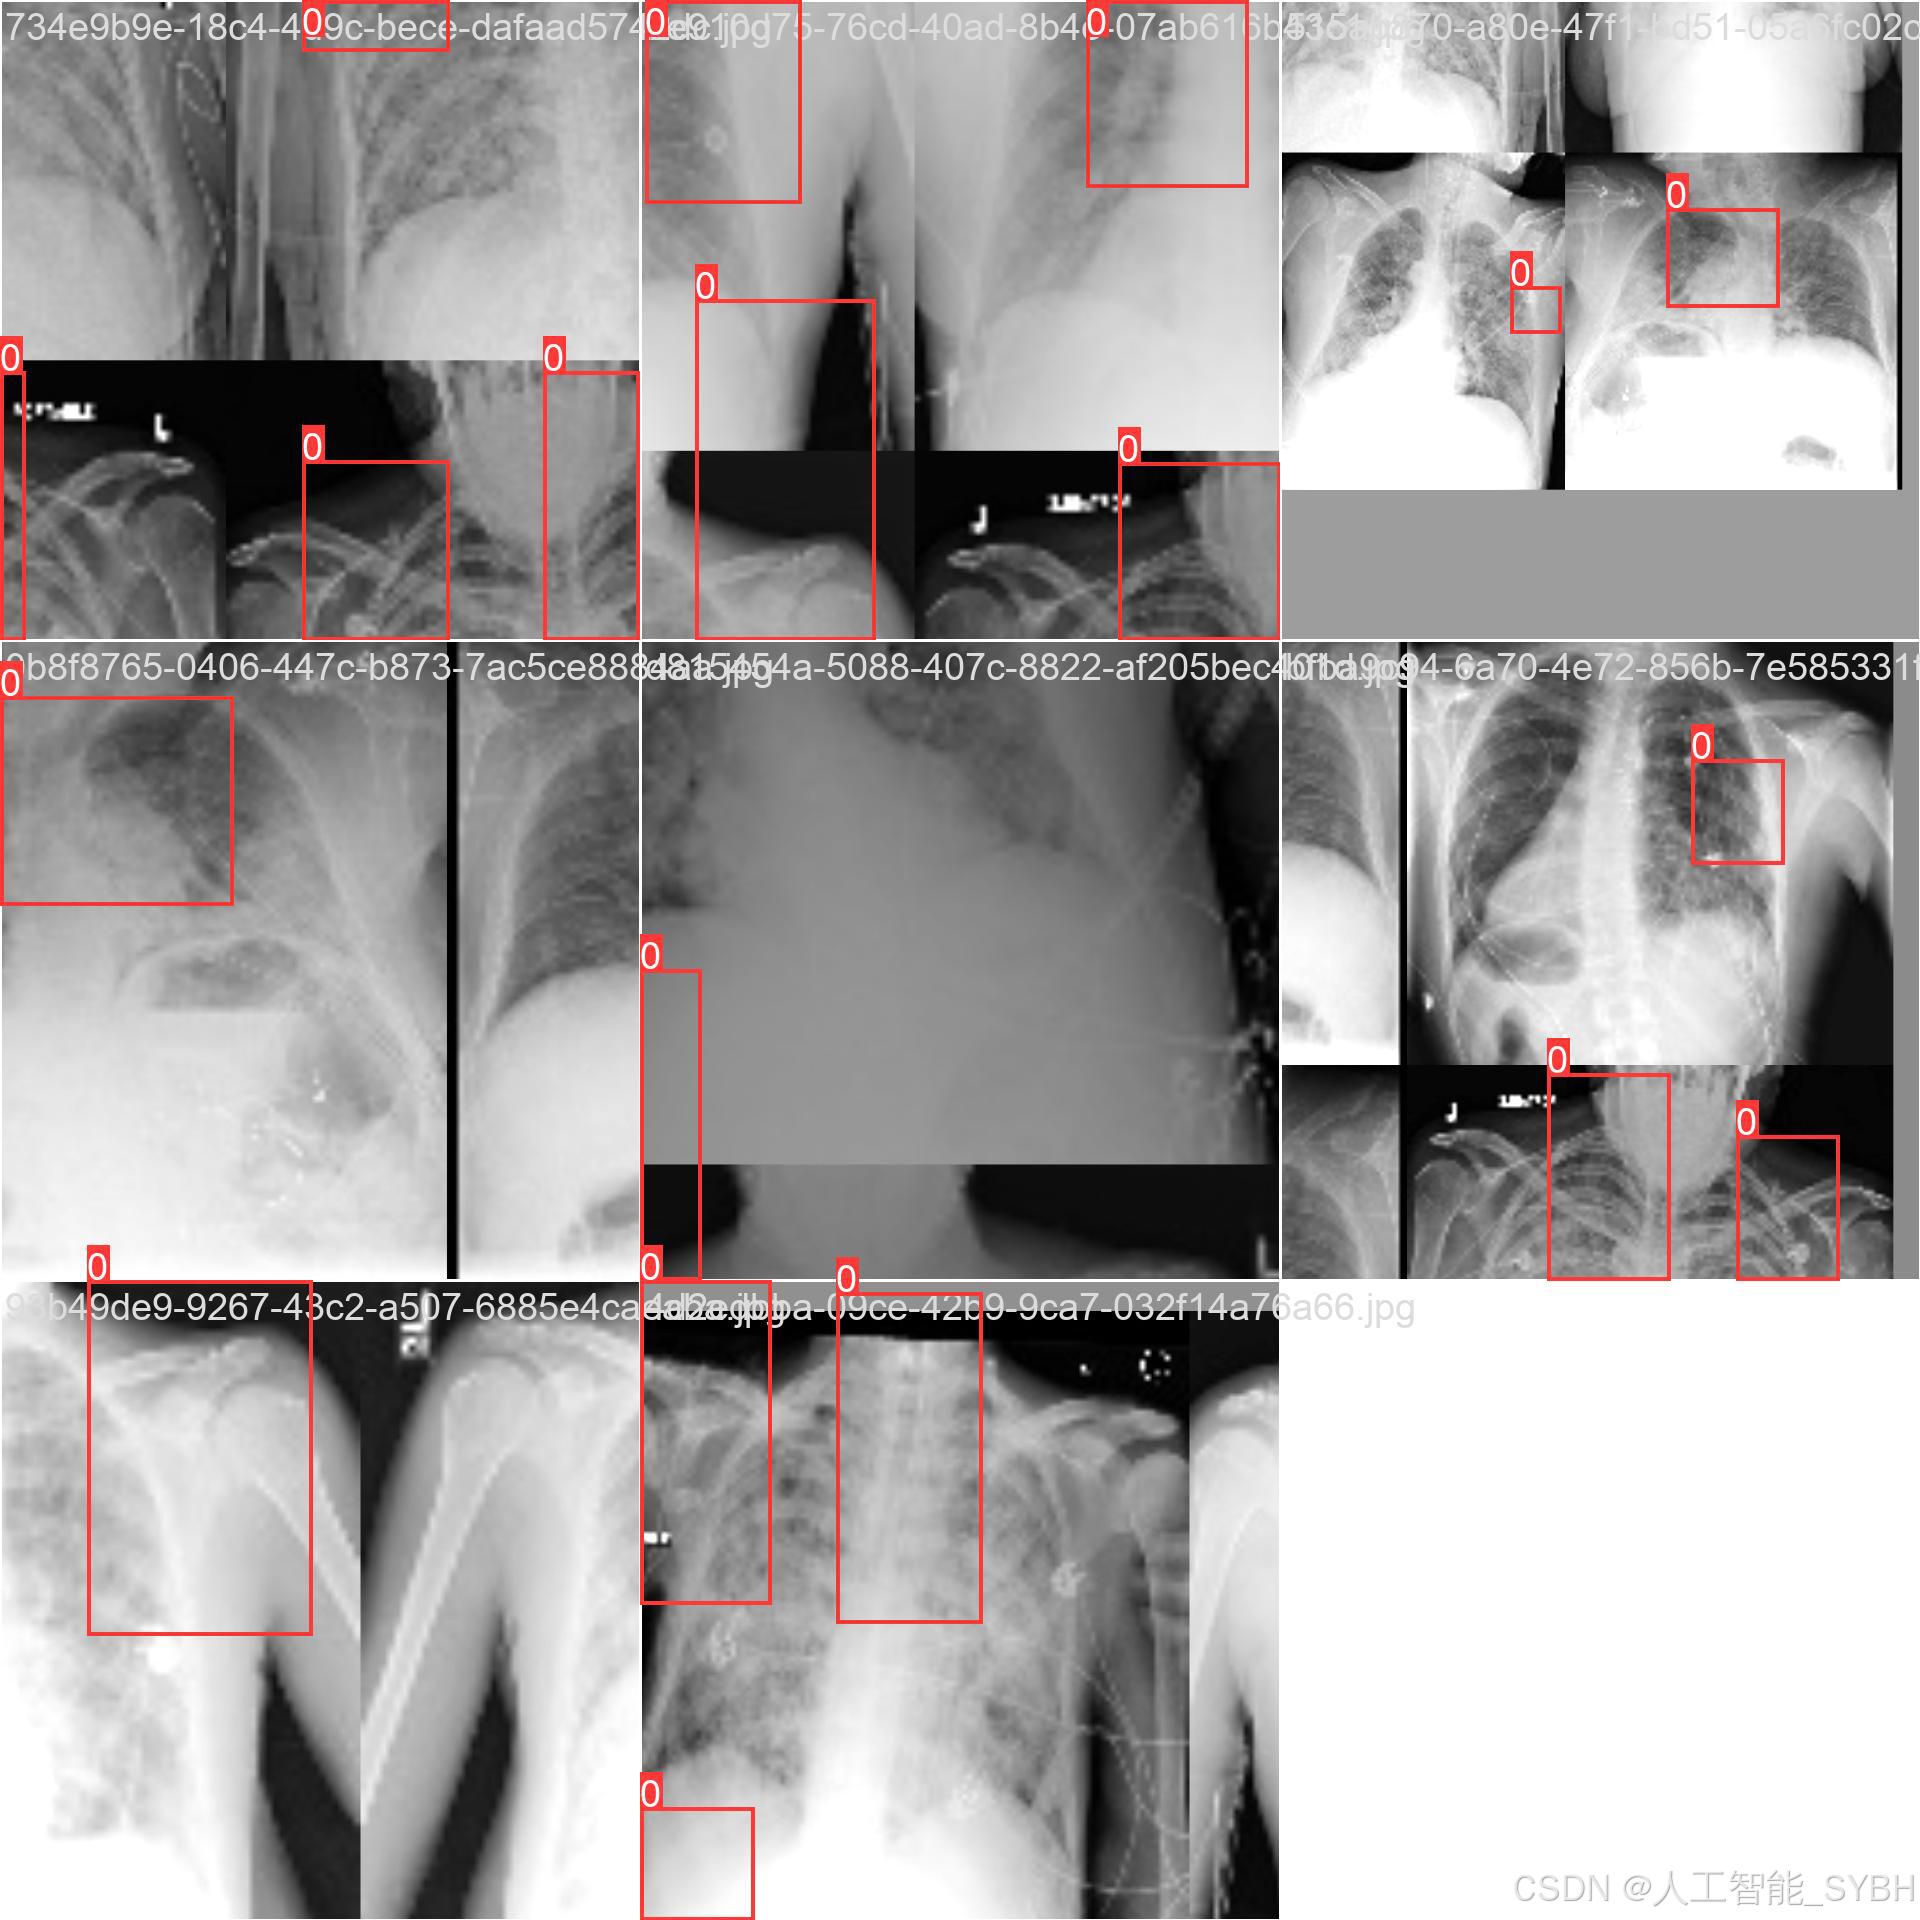

数据集名称: 肺炎检测数据集

数据集内容:

类别数量 (nc): 1类

类别名称: ['Pneumonia']

Pneumonia: 肺炎

数据集规模:

训练集: 3772张图像

验证集: 539张图像

测试集: 1078张图像

数据来源:

数据集通过收集医院中的胸部X光片构建,涵盖了不同年龄段、性别和病情的患者,以确保模型的泛化能力。

数据标注:

每张图像中的肺炎区域均使用边界框(Bounding Box)标注,并标注对应的类别。

数据集特点:

多样性: 数据集包含不同患者的胸部X光片,覆盖了多种病情和拍摄条件。

高质量: 图像分辨率高,标注精确,适合深度学习模型的训练。